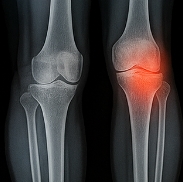

4. 영상 검사 (X-ray, 초음파, CT)

관절 변형, 토피(요산 결절), 염증 범위를 평가하기 위해 시행됩니다. 초음파에서는 관절 주변의 미세한 요산 침착도 확인 가능하며, CT는 장기적 손상 여부를 정밀하게 파악할 수 있습니다.